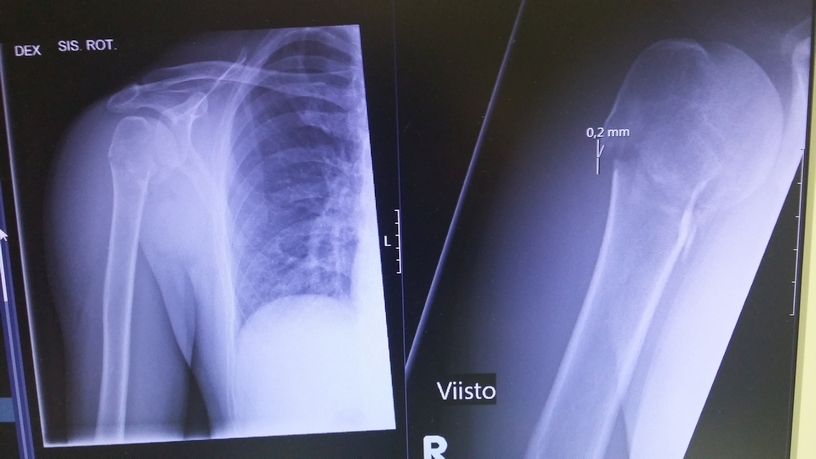

Life hurts

You know what... During the past two decades it hasn't been too many times that I have been on a sick leave, or unable to work on the game due to medical condition, wounds or injuries. But now a week ago I fractured my shoulder when falling of the horse during horseback archery training. Doctors orders are to wear arm sling for the next two weeks. After that a new xray will reveal how the recovery goes. Luckily no operation was needed. I just have to rest and wait, and so do you. So, I'll enter on a sick leave now and report back after two weeks.

I am mostly unable to answer to emails or at forums, but we'll try to handle the urgent cases somehow. Not to worry, I will survive. Game development and [URL="https://www.youtube.com/UgriArcher"] archery endeavours[/URL] to be continued when the doc says so.

My current wounds and injuries screen looks like this :)